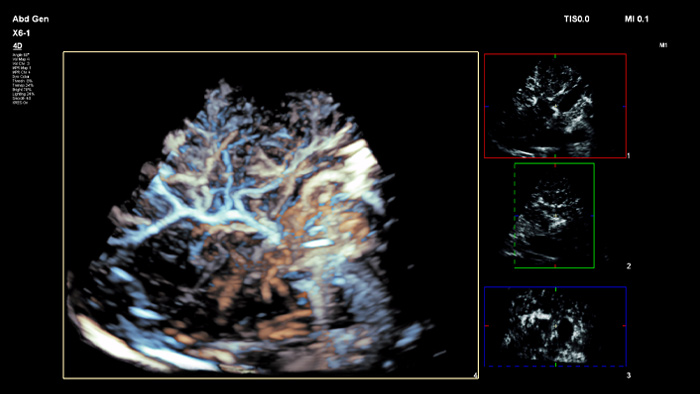

Treffen Sie auch in diagnostisch schwierigen Fällen die richtige Entscheidung mit den Philips Funktionen zur Bildfusion und Nadelnavigation. Ein effizienter Arbeitsablauf ermöglicht Klinikteams eine schnelle und effektive Fusion von CT/MRT/PET mit Live-Ultraschallbildern, wobei die Nadelnavigation die Biopsieführung bei kleinen, schwer zugänglichen Läsionen unterstützt.³

Mit der Tumorkontur können Anwender Läsionen mit einem halbautomatischen Tool planen und hervorheben. Es erleichtert das Zeichnen einer 3D-Kontur um die relevante Struktur und bietet so Unterstützung in schwierigen Fällen, bei denen die Läsion nicht einfach zu erkennen ist.